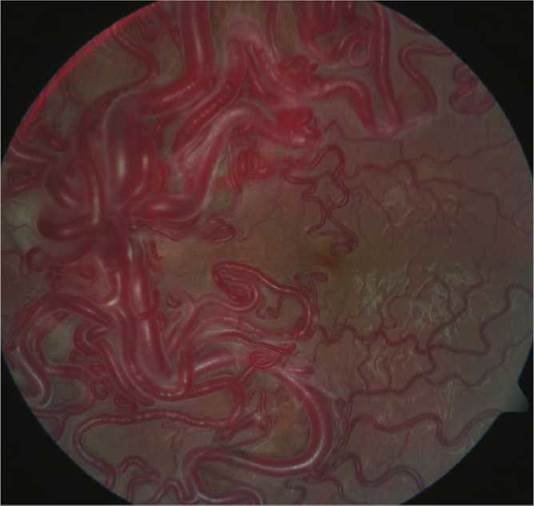

(See Figure 13.13.7.)

FIGURE 13.13.7 Racemose hemangioma.

Ocular. Enormously dilated, tortuous retinal vessels with arteriovenous communications without communicating capillary beds and without mass or exudate. Rarely, proptosis from an orbital racemose hemangioma.